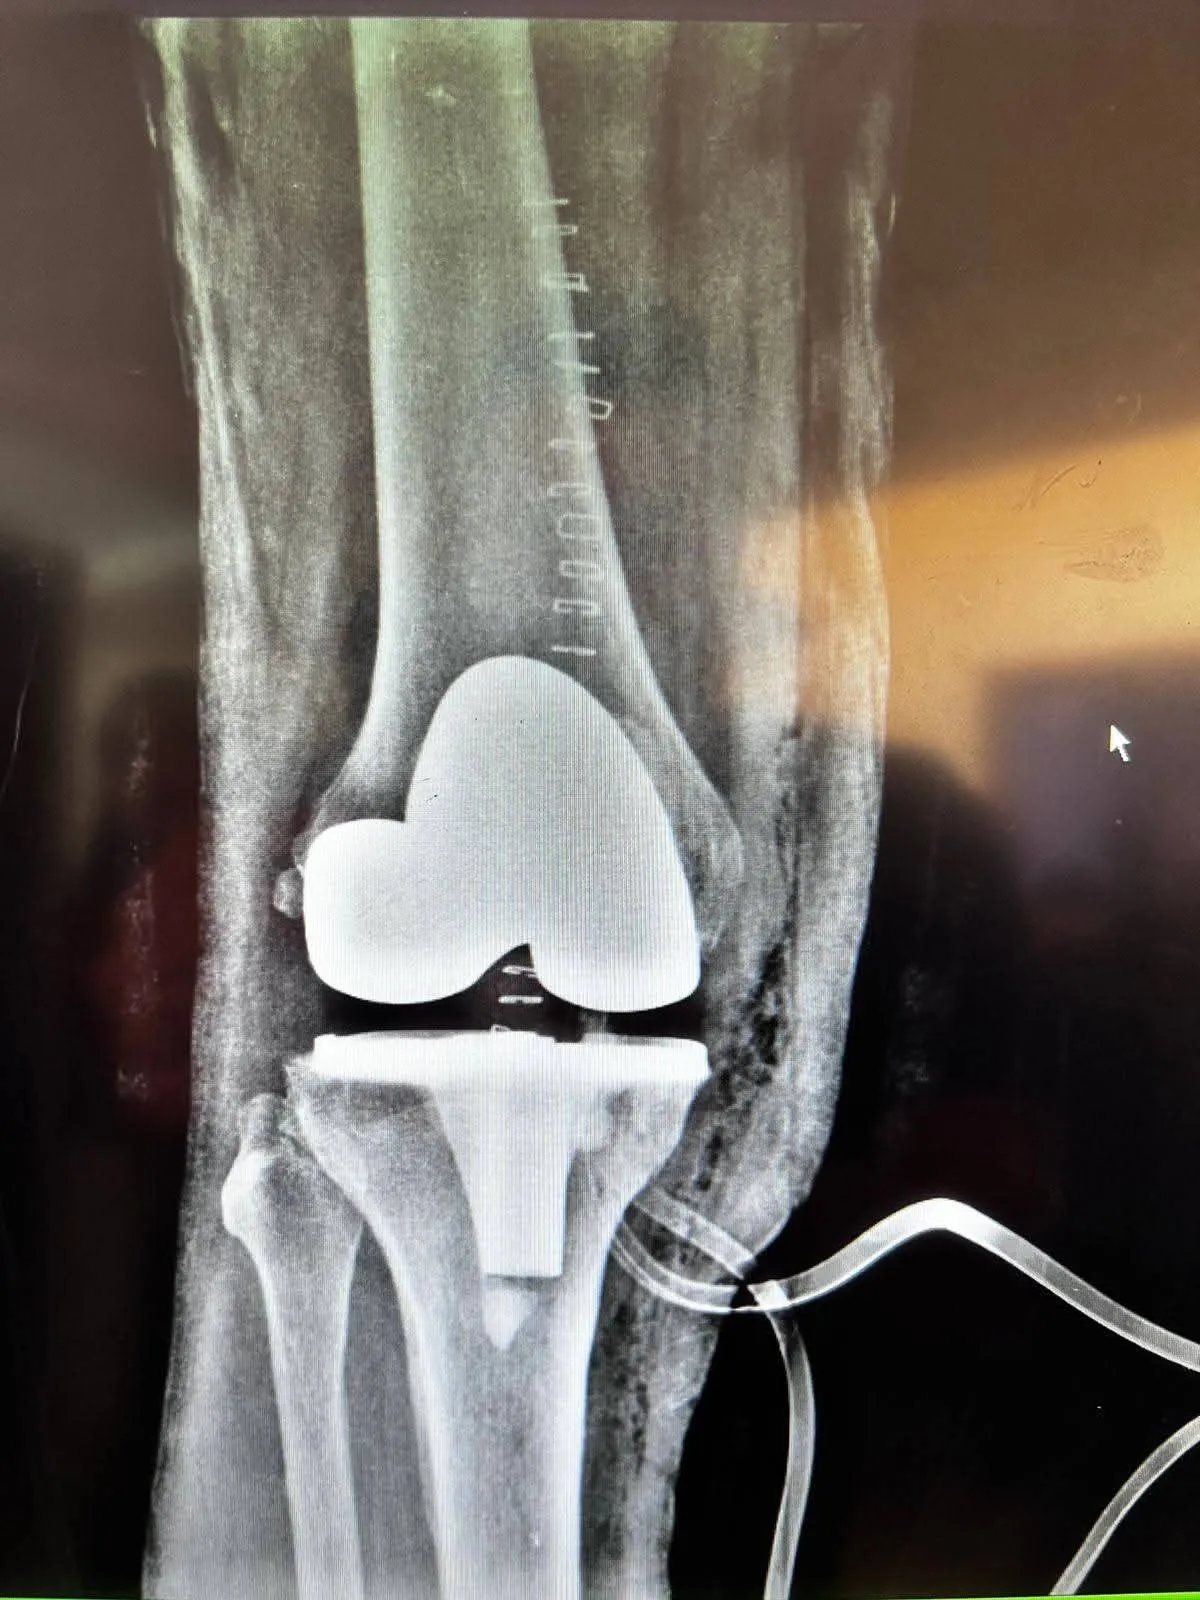

تدريسي في كلية طب المستنصرية يجري عملية تبديل مفصل الركبة بنجاح لمريضين في مستشفى اليرموك التعليمي

ضمن مبدأ الخدمة المجتمعية التي توفرها كلية الطب في الجامعة المستنصرية وبالتعاون مع مؤسسات وزارة الصحة ، أجرى التدريسي في فرع الجراحة بكلية الطب الجامعة المستنصرية / استشاري جراحة العظام والكسور الأستاذ المساعد الدكتور محمد جعفر الموسوي عملية تبديل مفصل الركبة بنجاح لمريضين في مستشفى اليرموك التعليمي .

وقال رئيس الفريق الطبي الدكتور محمد جعفر الموسوي : أُجريت عمليتا تبديل مفصل الركبة لمريضين تجاوزا الستين من العمر، كانا يعانيان من سوفان متقدم في مفصل الركبة ، مع أمراض مزمنة مرافقة زادت من تعقيد الحالة الجراحية.

وأضاف : كان المريض الأول يعاني من مشاكل قلبية سابقة أُجريت له خلالها قسطرة قلبية ، ويشكو من سوفان شديد في الركبة مع ألم مزمن لم يستجب للعلاج التحفظي ، تم إجراء عملية تبديل مفصل الركبة له بنجاح مع الأخذ بالاعتبار حالته القلبية ، أما المريض الثاني رجل يبلغ من العمر 65 عاماً ، يعاني من ارتفاع ضغط الدم والسكري وأمراض قلبية ، بالإضافة إلى سوفان شديد في الركبة اليمنى ، وقد خضع أيضاً لعملية تبديل المفصل بنجاح دون مضاعفات.

وتكللت العمليتان بالنجاح ، ويُتابع المريضان حالياً في ردهات المستشفى بحالة مستقرة مع تحسن ملحوظ في القدرة على الحركة ، بانتظار استكمال التأهيل البدني.